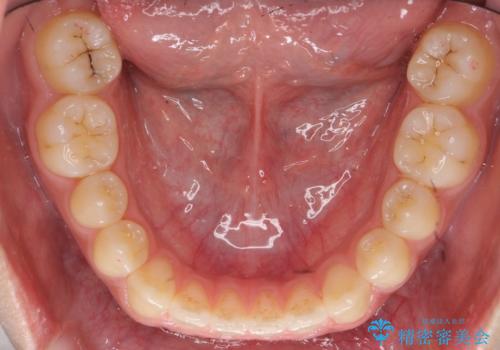

前歯のすきま 受け口 インビザラインで

治療症例の内容

- 治療計画

- 前歯のすき間を気にして来院。

受け口もあり、前歯が端同士であたる、切端咬合となっていました。

下の歯のすき間を閉じて上の歯の内側に入るように位置付けました。

すき間もきれいに閉じ、満足していただきました。

上の前歯は下の歯と直接へりが当たっていた状態(切端咬合)だったため、形がいびつだったのは、わずかにやすりがけをして整えました。

セラミックですき間を閉じようとすると、すきまをうめるために巨大な歯になり、また、下の歯が前に出て強く当たるため、セラミックがかけるおそれがあります。また、下の歯をさけようとすると角度をかえるために歯を極端に削らなければならなくなり、神経をとらなければいけなくなるリスクもあります。

このような歯並びは、セラミックでかぶせるよりは、矯正治療の

適応と言えます。